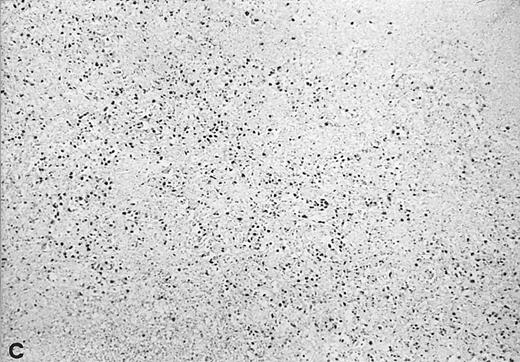

In situ hybridization with EBER probes. In a representative lymphadenopathy case (no. 20), rare EBER+ cells are seen, mainly in the interfollicular areas (A and B). In a representative lymphoma case (no. 46) nearly half of the cells are EBER+ (C and D). Original magnification: ×130 (A and C) and ×260 (B and D).

Twelve of the 16 EBV+ lymphoma samples scored from 3+ to 6+ for EBV DNA content (ie, 102- to 105-fold higher than that found in the majority of the lymphadenopathy samples), and most were also positive by Southern blot analysis (Table 4). Seven of 11 tested samples were also positive for viral sequences by in situ hybridization with EBER probes (Table 4). Although the high content of EBV in these tumors strongly indicated that they arose from the proliferation of EBV+ cells, 4 large cell lymphomas contained consistently low levels of EBV DNA, a finding that might reflect either a dilution effect by nonneoplastic EBV− cells in the analyzed samples, or the presence of few infiltrating reactive EBV+ B cells.